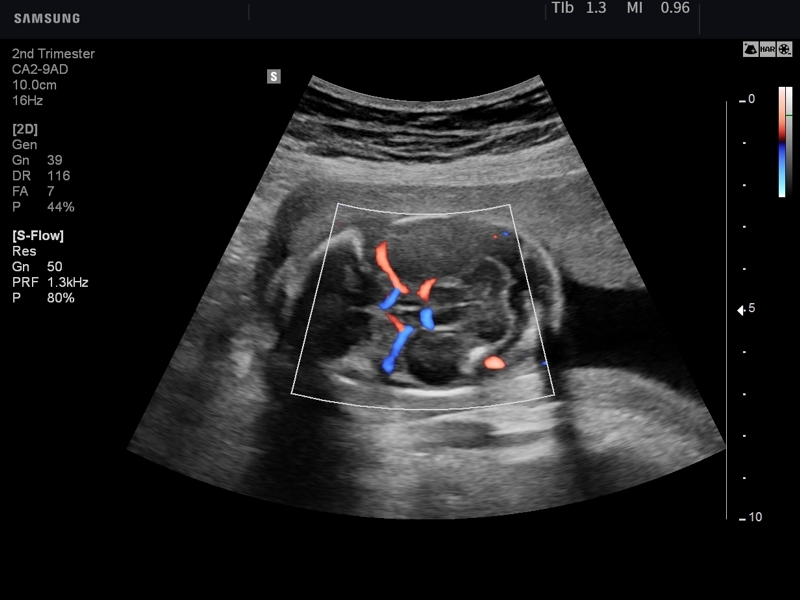

• S-Flow – технология цветового допплеровского картирования с повышенной чувствительностью.

• Конвексный датчик Samsung Medison CA2-9AD